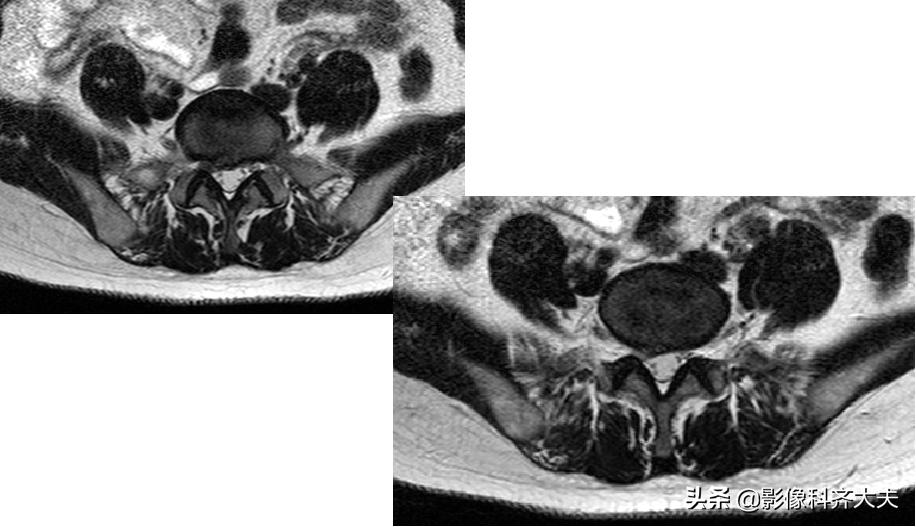

MRI:椎间盘突出(外侧型)

MRI:腰椎间盘右后突出